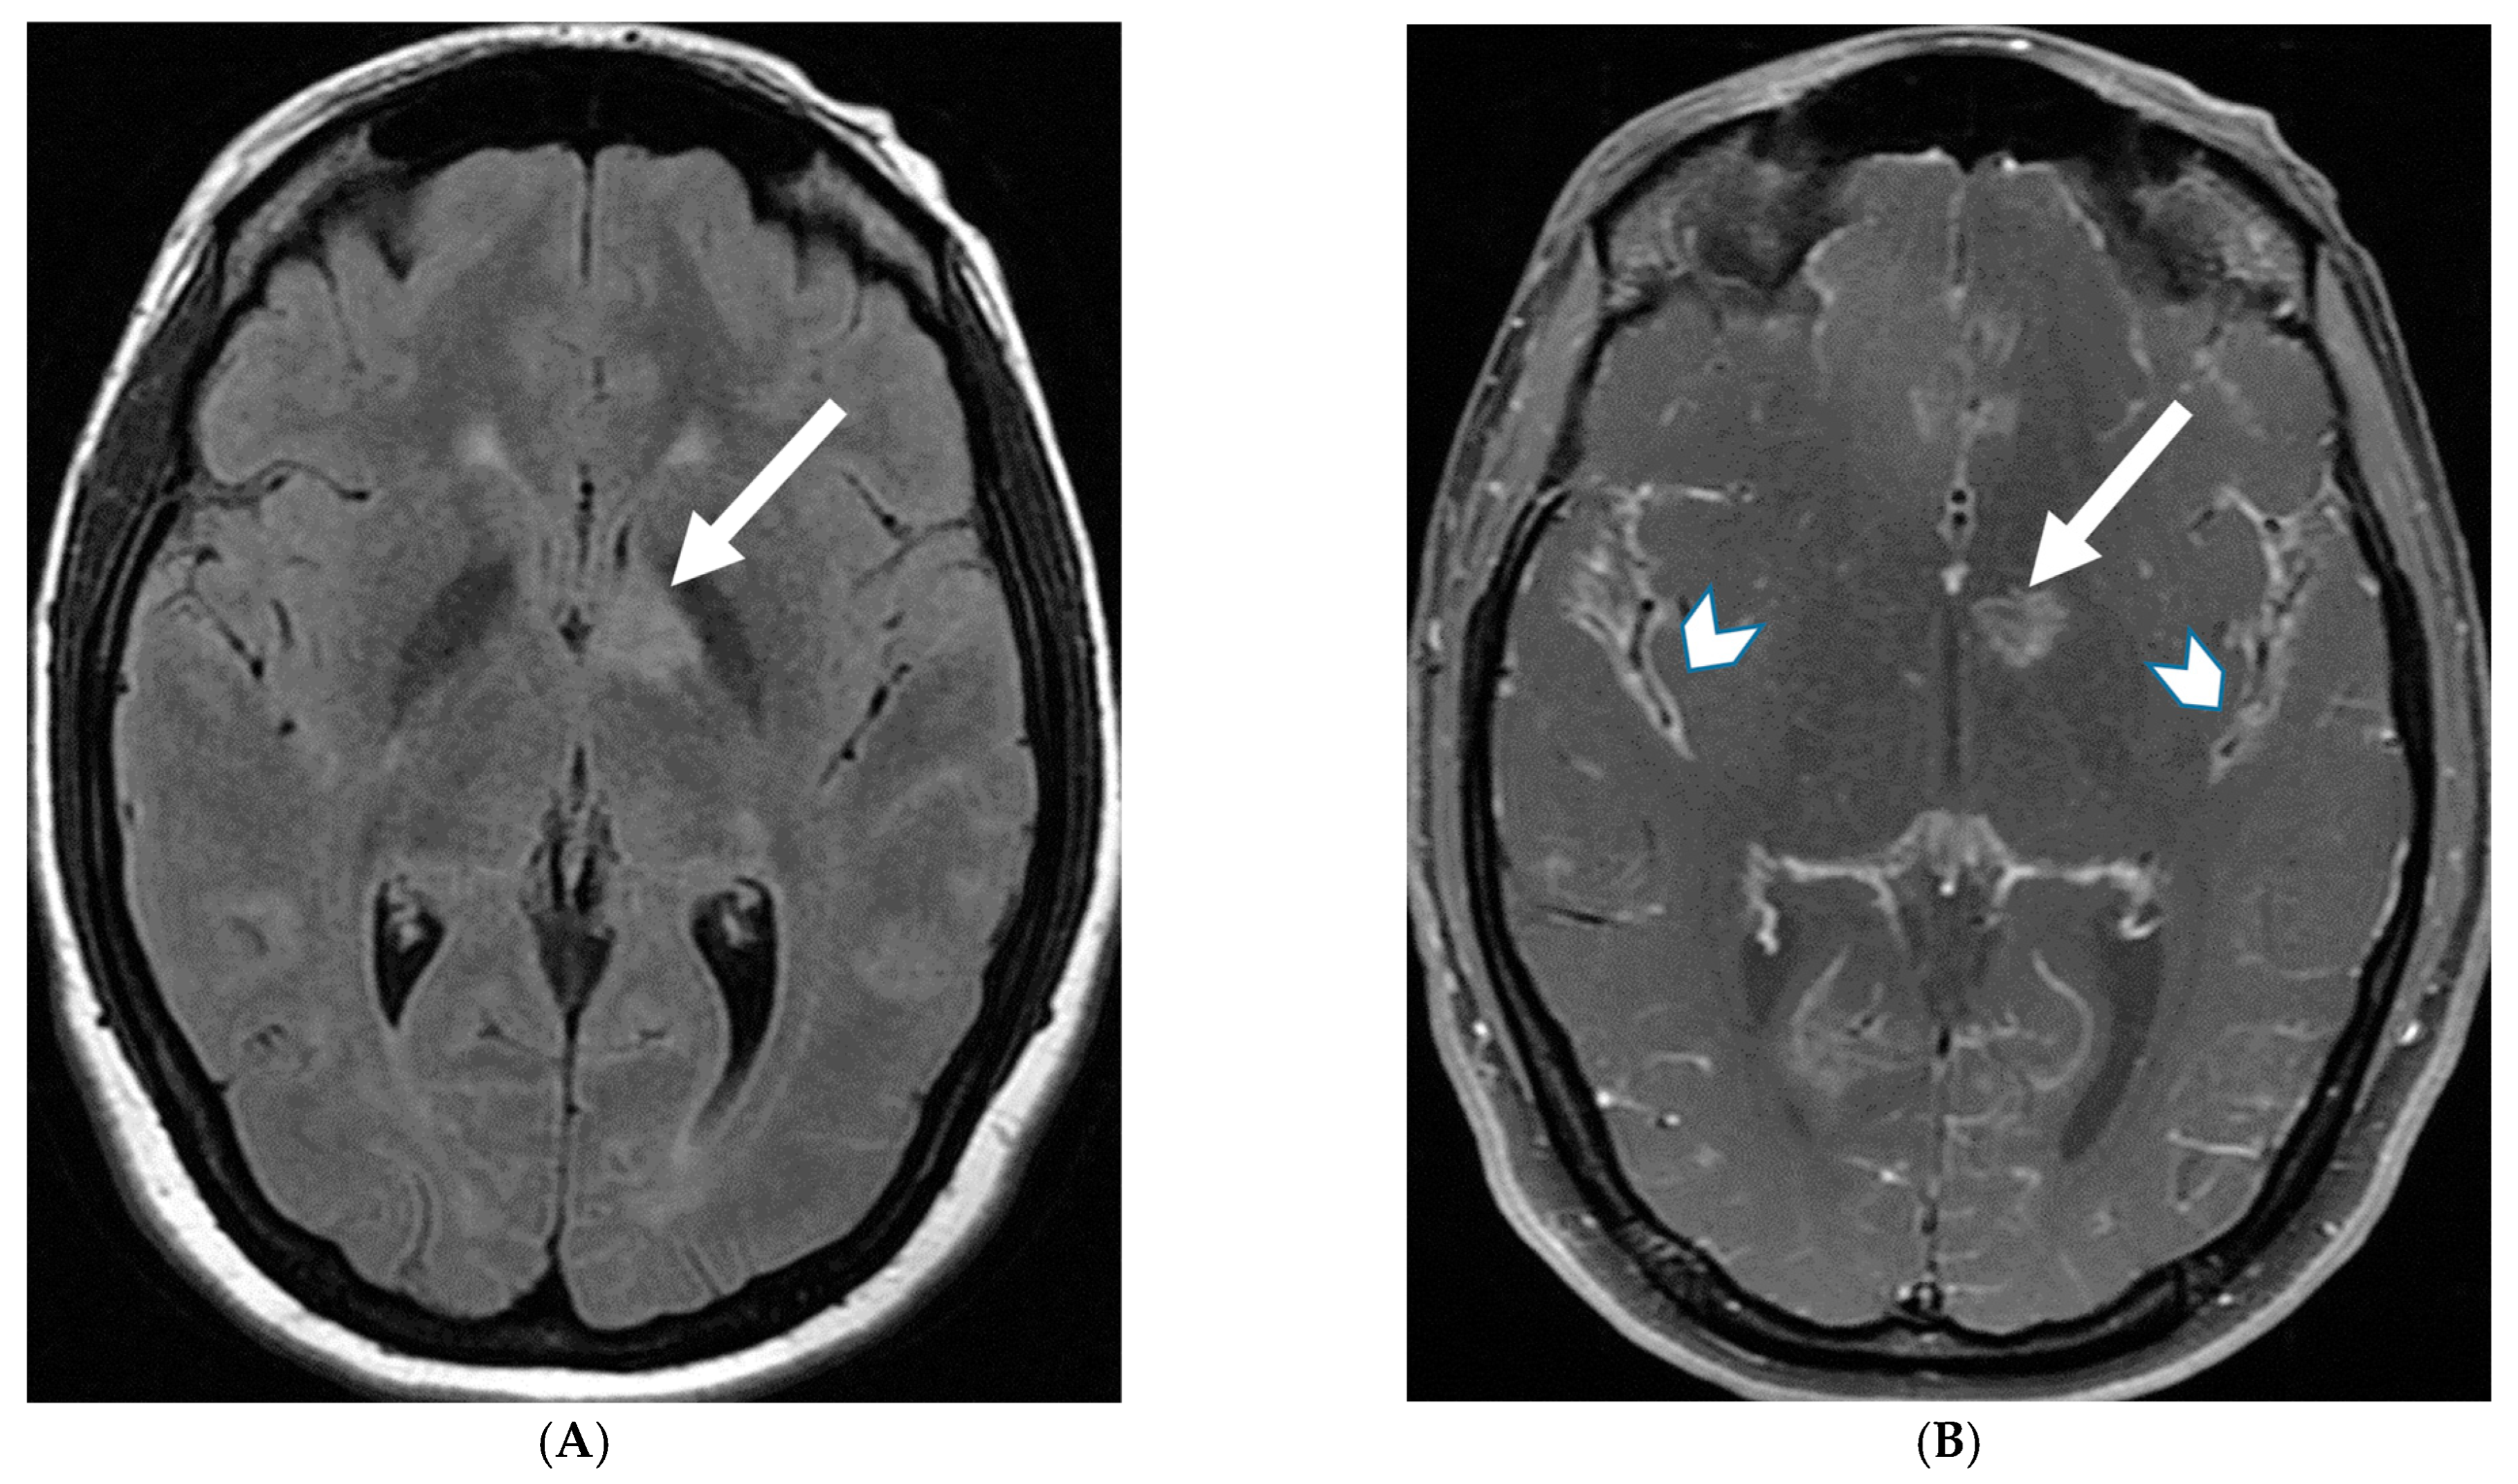

Figure 3.

18-year-old presented with headache, persistent vomiting and weight loss. History of sarcoidosis diagnosed 2 years ago. Axial Fluid Attenuated Inversion Recovery (FLAIR) (A), Axial T1 post contrast (B), Axial T1 inversion recovery post contrast (C) and Coronal Positron Emission Tomograpy (PET) scan (D): There is a heterogeneously enhancing ill-defined area of T2/FLAIR hyperintensity involving the medial aspect of the left globus pallidus (arrows), anterior aspect of the left thalamus and left hypothalamic region. Diffuse enhancement of the basal meninges, tentorium, throughout perisylvian sulci (arrow heads), along the infundibulum, and posteriorly at the craniocervical junction. There is also enhancement along optic nerve sheath (dashed arrows). Features are highly consistent with extensive neurosarcoidosis given the previous history of thoracic sarcoid. PET scan from 2 years earlier demonstrating avid uptake of radiotracer (curved arrows). Radiologically, the differential diagnosis includes tuberculosis and metastatic process. Patient made complete recovery after treatment for sarcoid.